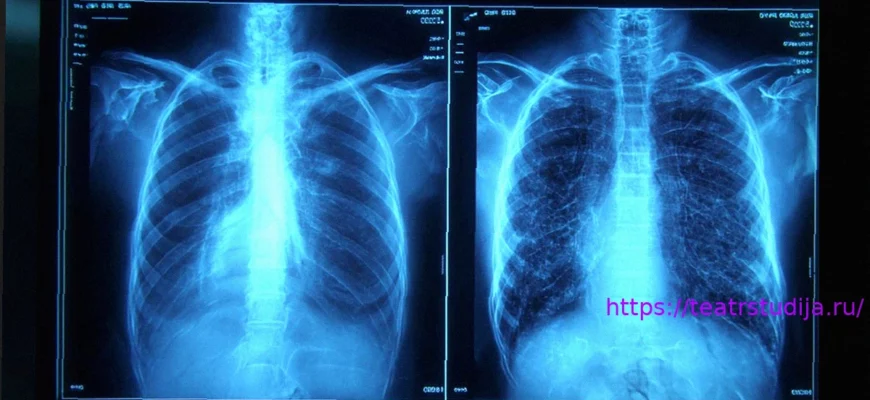

- Признак «слишком совершенного»: Дипфейковые рентгеновские снимки часто выглядят неестественно симметричными; кости слишком гладкие, позвоночники «слишком прямые», а переломы выглядят «необычно чистыми».

Первый набор данных включал реальные изображения и изображения, сгенерированные ChatGPT, различных анатомических областей. Второй набор данных состоял из рентгеновских снимков грудной клетки — половина подлинных, а другая половина создана RoentGen, генеративной моделью ИИ с открытым исходным кодом, разработанной исследователями Стэнфордской медицины.

«Дипфейковые медицинские изображения часто выглядят слишком идеально», — сказал доктор Торджман. «Кости чрезмерно гладкие, позвоночники неестественно прямые, лёгкие слишком симметричные, рисунок кровеносных сосудов чрезмерно однородный, а переломы выглядят необычайно чистыми и последовательными, часто ограниченными одной стороной кости».